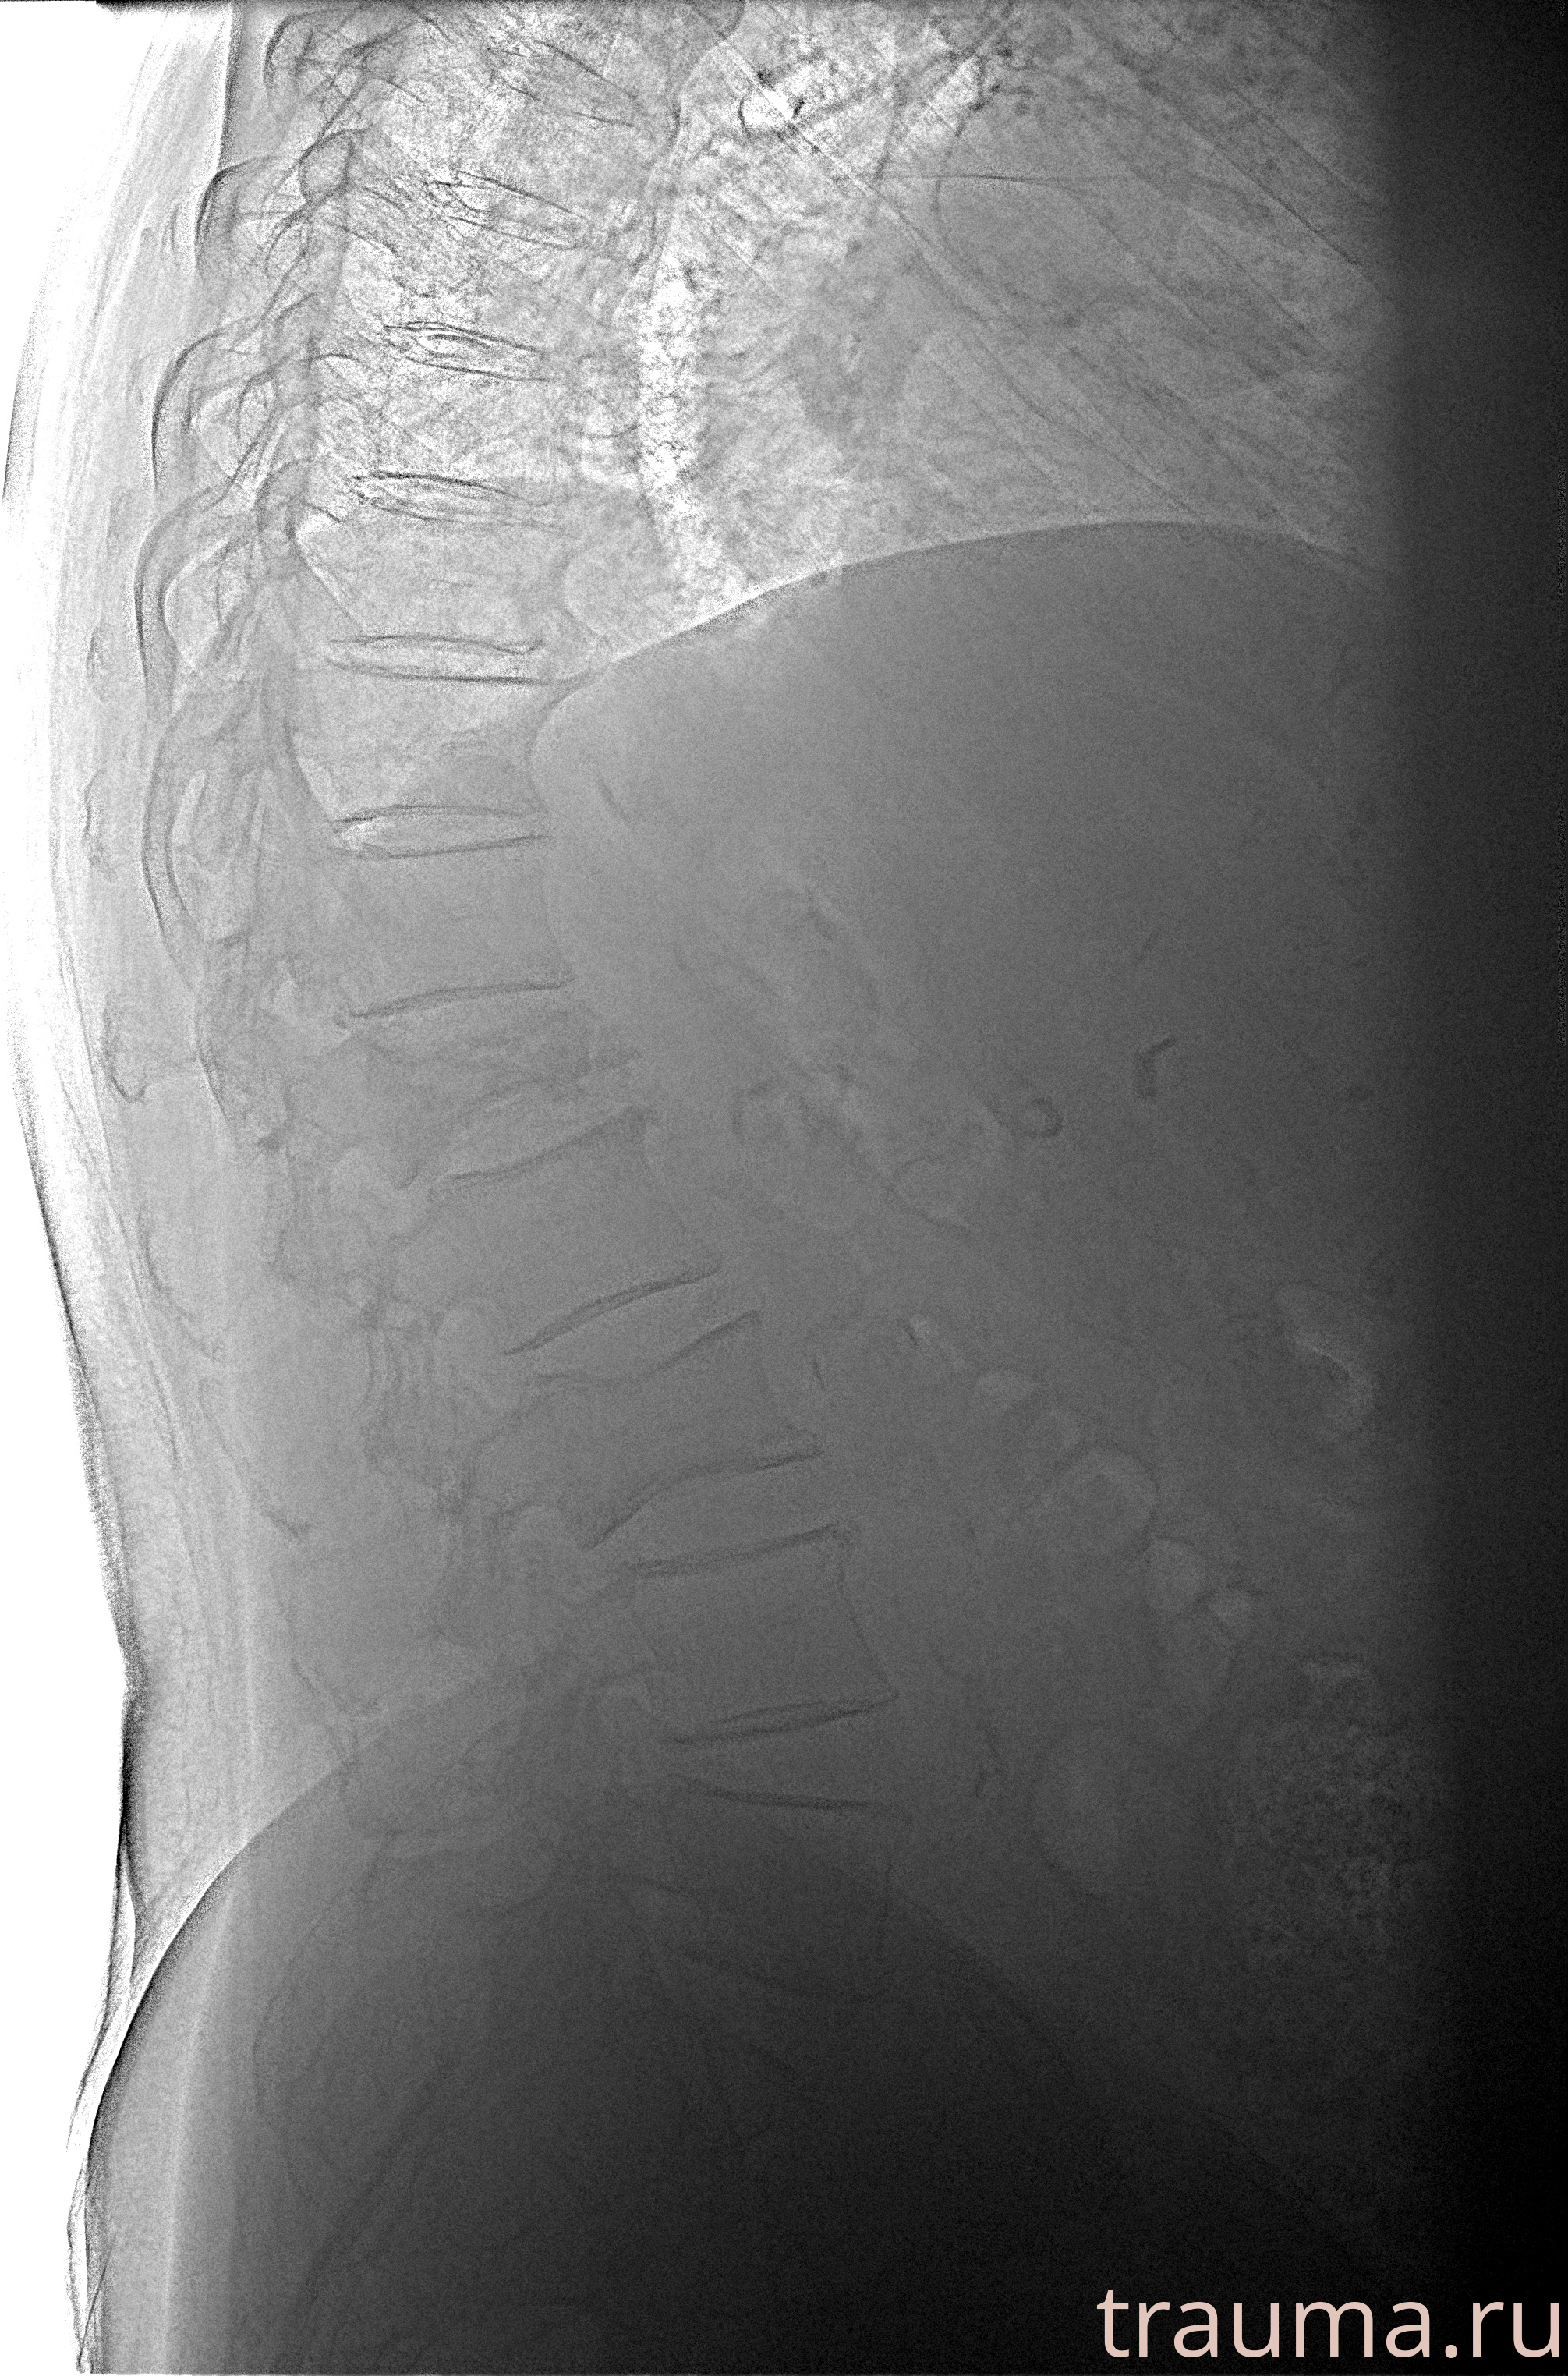

Рентгенограммы

Рентген на дому: по вашему адресу приезжает врач-рентгенолог, травматолог-ортопед с мобильным рентгеновским аппаратом, проводит диагностику травмы или заболевания, делает необходимые рентгенограммы, дает рекомендации по дальнейшему лечению. Получить качественные снимки в домашних условиях возможно благодаря уникальной методике, разработанной МосРентген Центром для института  Склифосовского